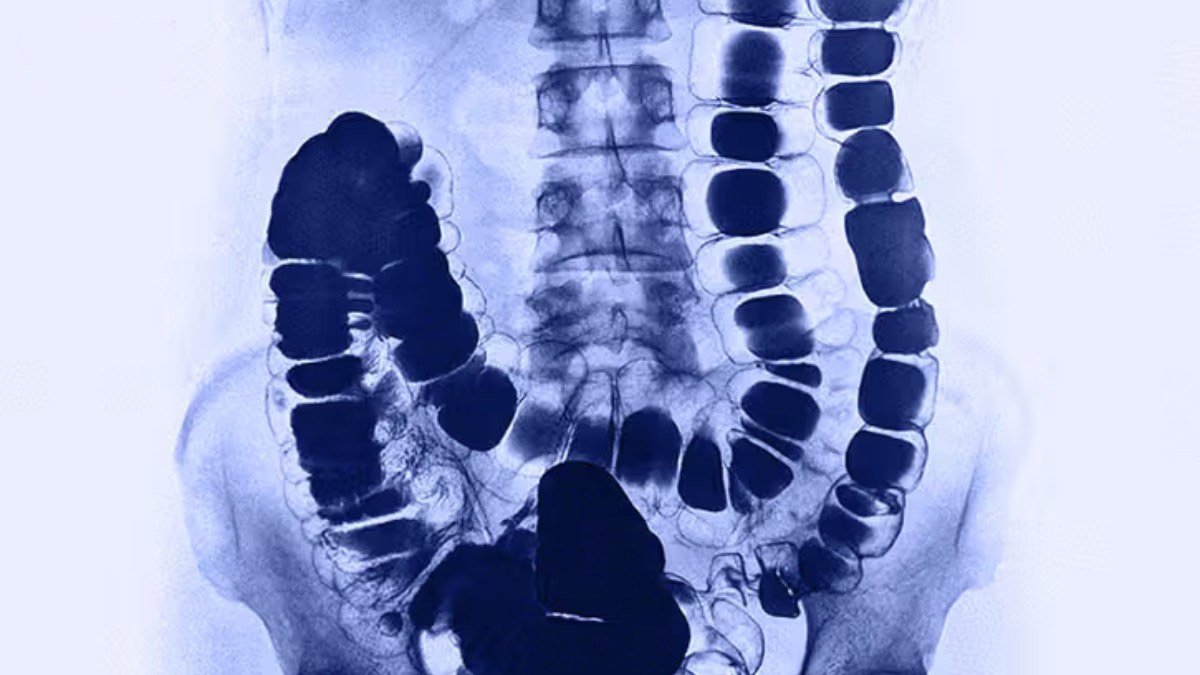

Lower gastrointestinal (GI) tract radiography, also called a lower GI or barium enema, is an x-ray examination of the large intestine, also known as the colon. This examination evaluates the right or ascending colon, the transverse colon, the left or descending colon, the sigmoid colon and the rectum. The appendix and a portion of the distal small intestine may also be included.

Fluoroscopy makes it possible to see internal organs in motion. When the lower gastrointestinal tract is filled with barium, the radiologist is able to view and assess the anatomy and function of the rectum, colon and sometimes part of the lower small intestine.